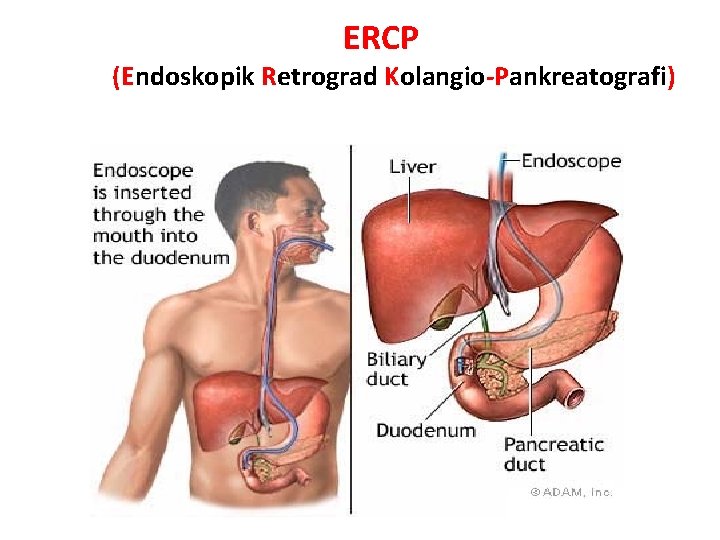

ERCP (Endoskopik Retrograd Kolangio-Pankreatografi)